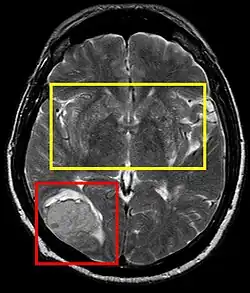

Stroke brain (similar to cerebral softening)

Cerebral softening, also known as encephalomalacia, is a localized softening of the substance of the brain, due to bleeding or inflammation. Three varieties, distinguished by their color and representing different stages of the disease progress, are known respectively as red, yellow, and white softening.[1][2]